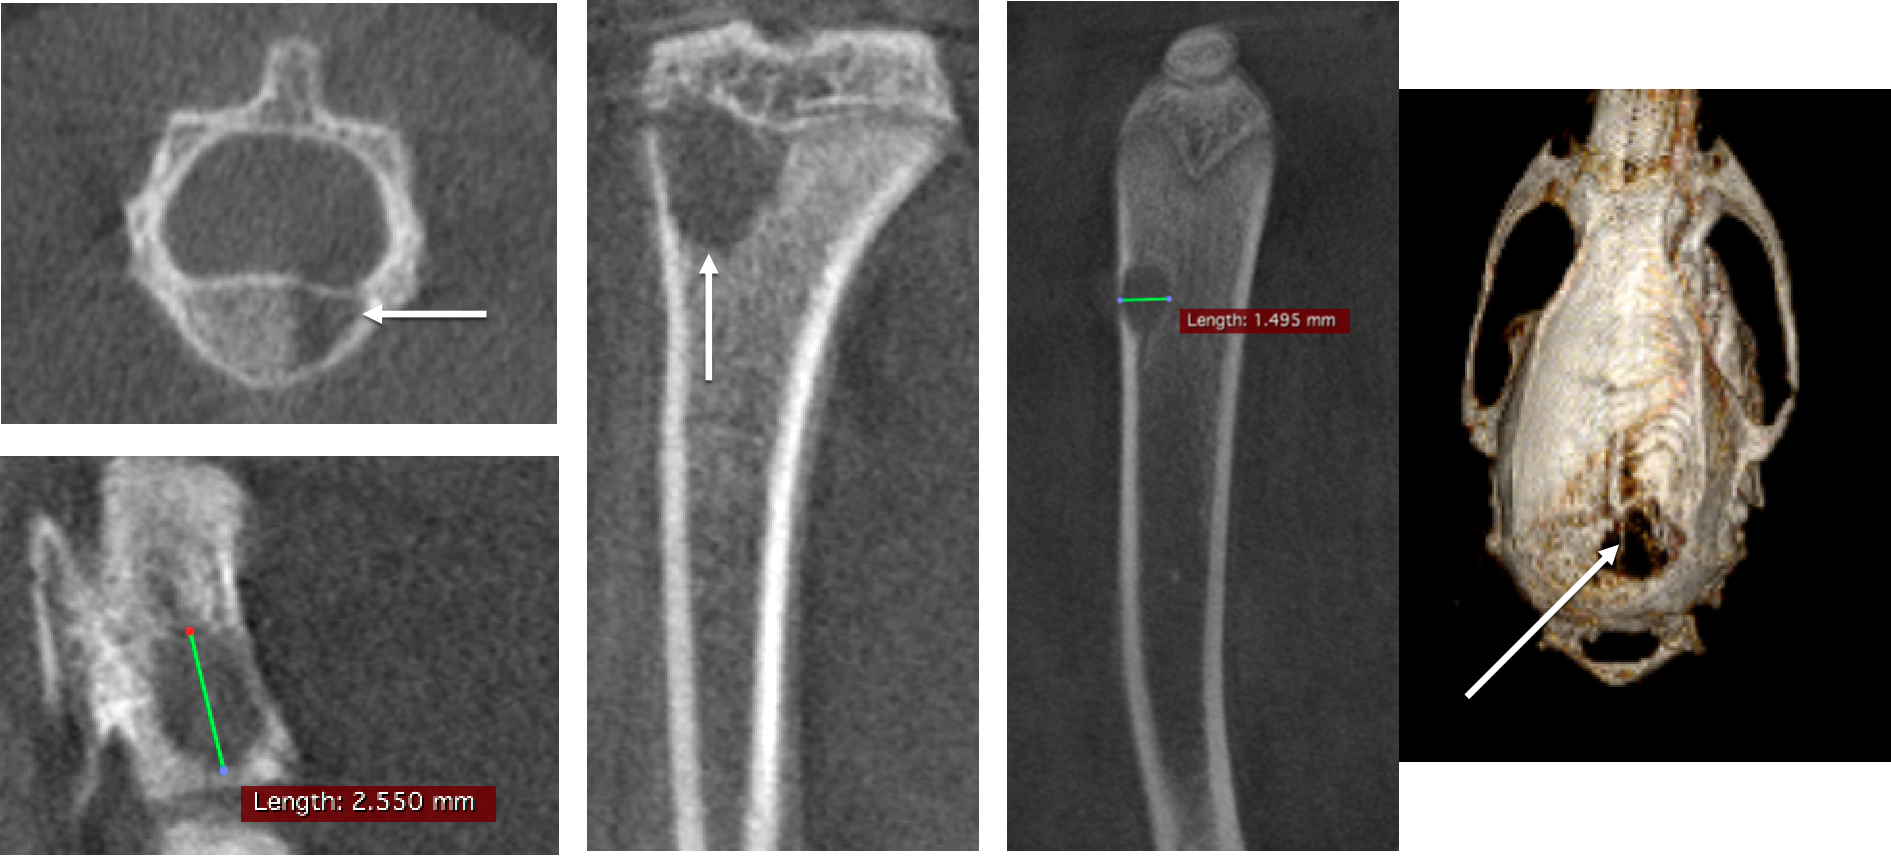

4、骨骼CT成像

骨骼腫瘤研究:大鼠活體CT顯示腫瘤引起腦轉移和骨轉移,骨骼中產(chǎn)生大量空洞,F(xiàn)DK重建,50μm voxel size。

骨轉移.png

用PMOD軟件進行骨骼數(shù)據(jù)處理:在CT的掃描成像圖上選擇感興趣區(qū)域(region of interest,ROI)做閾值分割等操作,可以將皮質骨(骨密質)和骨小梁(骨松質)進行分割,分別提取到不同組織區(qū)域,從而對它們的各種形態(tài)學特性進行研究和分析。

骨骼分析.png